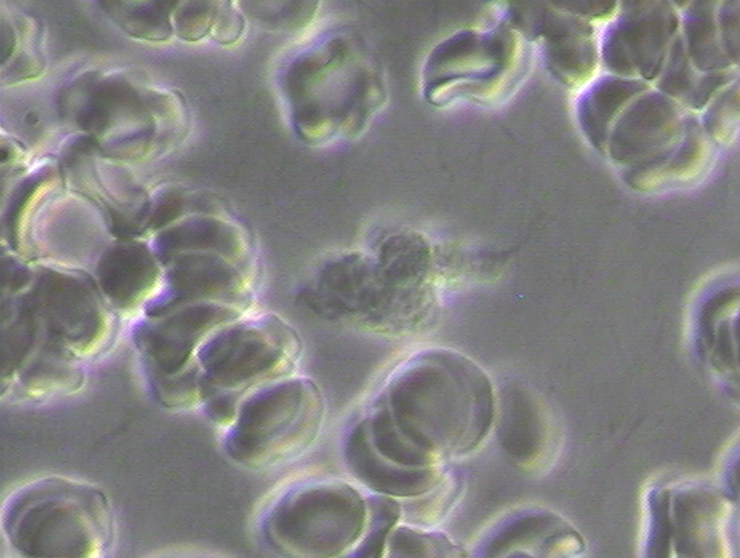

What Should Healthy Red Blood Cells Look Like?

Normal healthy red blood cells should be even in color, even in shape and finally even in size. (Phase Contrast Micrograph 5) Keeping the red bloods cells separated is critical so they can enter the pulmonary capillaries that lead to the alveolus sacs where the red blood cells eliminates acidic waste of carbon dioxide and lactic acid and adsorb and then absorb life-giving oxygen into the hemoglobin molecule. The following phase contrast micrograph is what normal healthy red blood cells should look like![12]

Live and Dried Blood smears are both non-invasive blood tests that were used in viewing anatomically the conditions of the red and white blood cells in Disseminated Intravascular Coagulation (DIC), Thrombosis, Rouleau, the ‘Corona Effect’ and Acanthocytosis. (See Phase Contrast Micrograph 7)[12]